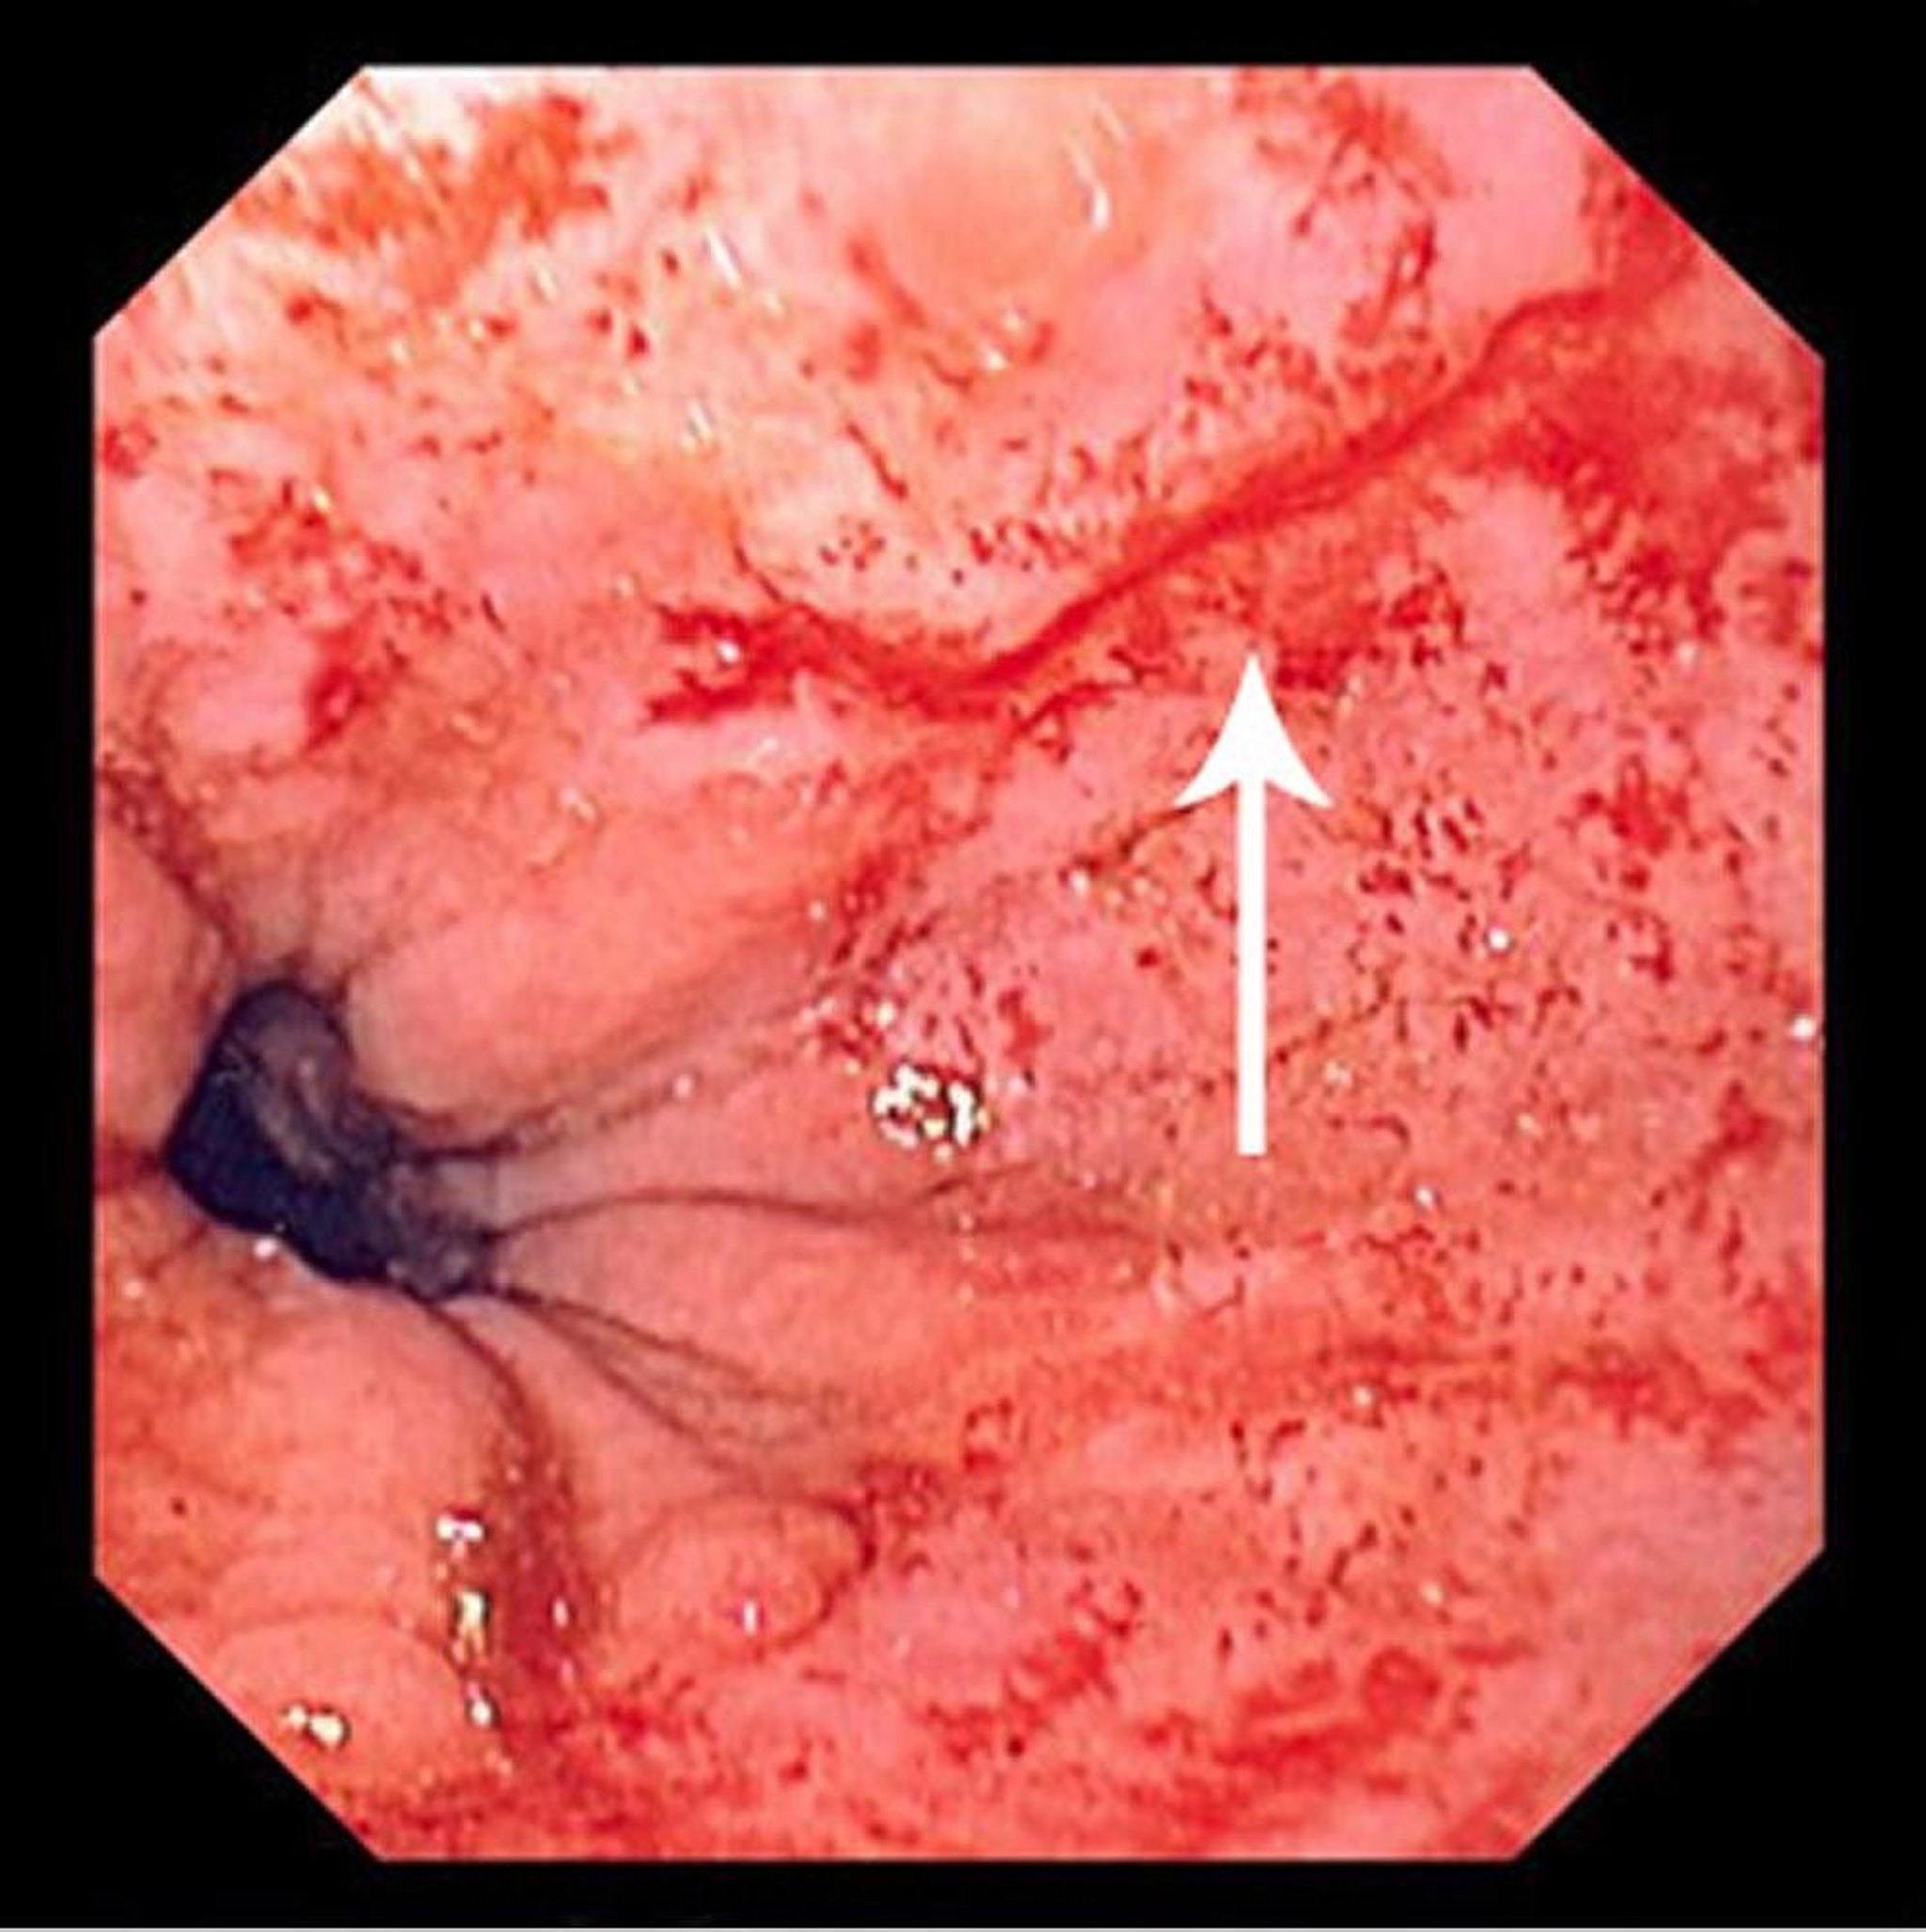

Mallory-Weiss Tear

This photo shows a thin Mallory-Weiss tear (arrow).

Photo provided by David M. Martin, MD.